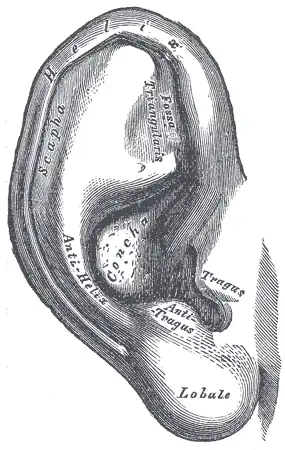

.jpg) A cross section of mammalian elastic cartilage | |

Lateral side of the auricle | |

Elastic cartilage, fibroelastic cartilage or yellow fibrocartilage [1] is a type of cartilage present in the pinnae (auricles) of the ear giving it shape,[2] provides shape for the lateral region of the external auditory meatus,[3] medial part of the auditory canal[3] Eustachian tube, corniculate and cuneiform laryneal cartilages,[3] and the epiglottis. It contains elastic fiber networks and collagen type II fibers.[4] The principal protein is elastin.